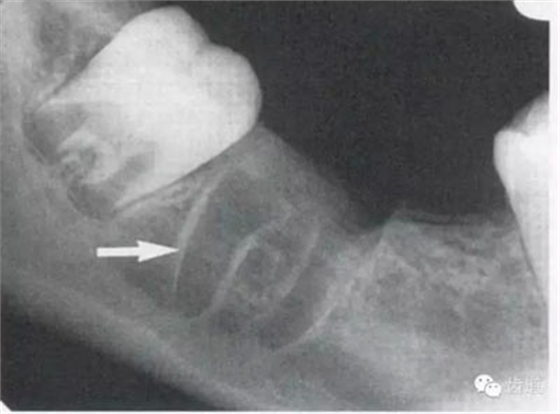

4)外斜線:

由升支前緣下部斜向前下方,為一密度高的帶狀影像。常重疊在第二、三磨牙牙冠處、頸部或根部,使牙髓室或根管不能清晰顯示

7)下頜角區(qū):

在下頜管的后下區(qū)域,骨小梁稀少,這是正常骨質(zhì)疏松區(qū)域 8)頦嵴:

9)內(nèi)斜線:

為自頦嵴斜向上后的致密線條影,至升支前緣消失,位于外斜線之下,走行方向與其一致。